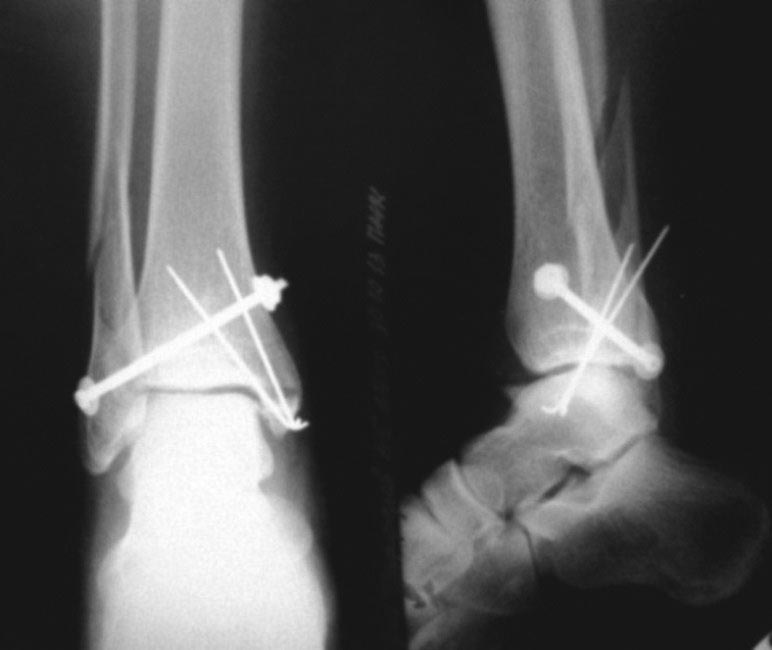

Здравствуйте, 18.10.13 подскользнулся и сломал правую лодыжку, описание рентгенолога:Перелом внутренней лодыжки без смещения, сложный перелом и/з диад** м/берцовой кости, со смещением, отрыв основания б/берцовой кости без смещения.29.10.13 была проведена операция остеосинтеза правого голеностопа, сделан снимок наложена лангета и я отправлен домой на 1 месяц. Вопрос правильно ли проведена операция и когда я смогу самостоятельно ходить без костылей и не стану ли я инвалидом?

В общем, форма голеностпоного сустава правильная. Насчет самостоятельной ходьбы без костылей - это уж Вы как раз сами расскажете, когда смогли ходить без них.